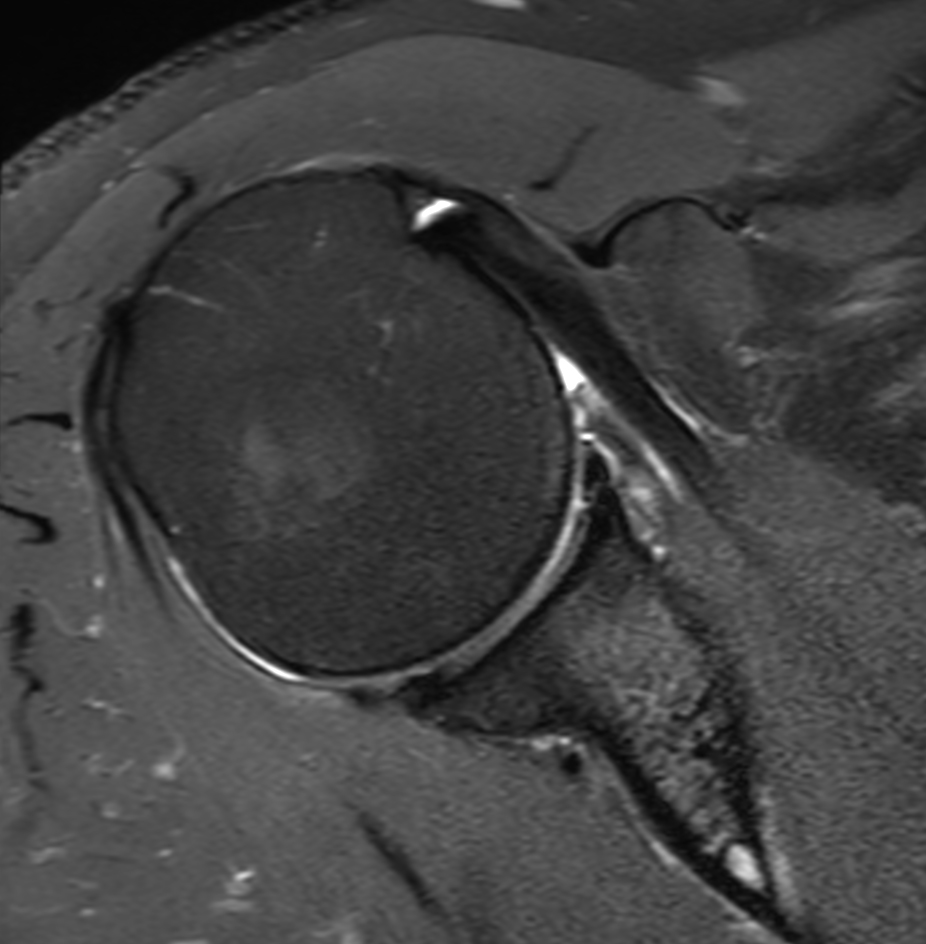

High resolution imaging with the dS 16ch Shoulder coil and Compressed SENSE